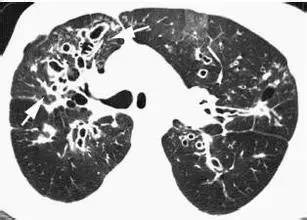

结核,高分辨率CT显示右肺周围边界不清,大小不等,这些征象代表了支气管内结核的播散

非结核分歧杆菌感染:高分辨率的CT扫描显示右肺多个结节分布于分支线状影周围,支气管扩张壁增厚,黏液嵌塞,支气管肺泡灌洗确诊。